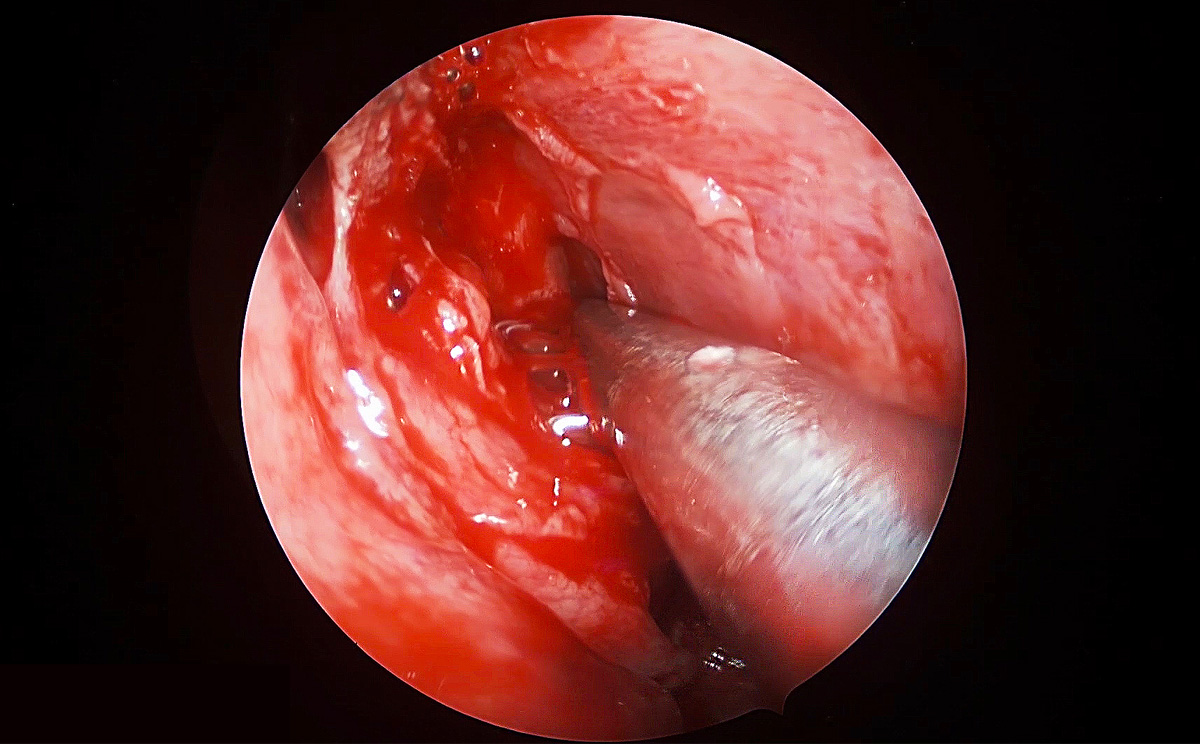

此次手術(shù)采用內(nèi)窺鏡下經(jīng)鼻進路行腦垂體瘤切除術(shù),使用機器益柯達4K超高清內(nèi)窺鏡攝像系統(tǒng),分辨率可達3840X2160P,是全高清內(nèi)窺鏡分辨率(1920X1080P)的4倍,該產(chǎn)品具有出色的色彩還原功能,能夠精細的顯示手術(shù)中的細微血管、神經(jīng)、筋膜層次,使手術(shù)更精準、安全。